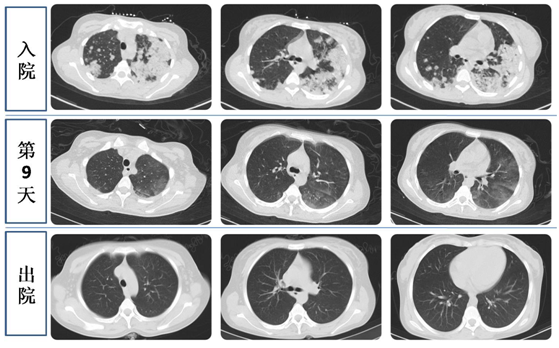

血红蛋白仅为正常参考值的四分之一,血小板为4X10^9/L(正常参考值为100-300X10^9/L),随时都有脏器出血的风险。血气分析提示I型呼吸衰竭,胸片存在双肺弥漫性渗出,肺部CT可见双肺部多发高密度影。

第9天,肺部CT提示双肺高密度影显著吸收,血红蛋白逐渐上升至70g/L,血氧分压正常。

经过30天的精心治疗后,拉姆的血红蛋白已经涨到100g/L,最后一次复查CT提示双肺病变完全吸收,笑容又重新回到这位年轻妈妈的脸上。